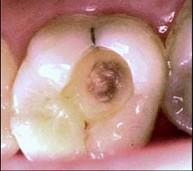

问题 患者女性,20岁。因左侧后牙进食时嵌塞食物疼痛就诊。检查:左上6面龋洞,探洞底敏感,叩(-),冷刺激入洞后疼痛,去除刺激立即消失,热测同对照牙。该牙诊断可能为 ( )

选项 A.浅龋 B.中龋 C.深龋 D.急性牙髓炎 E.慢性牙髓炎

答案 C